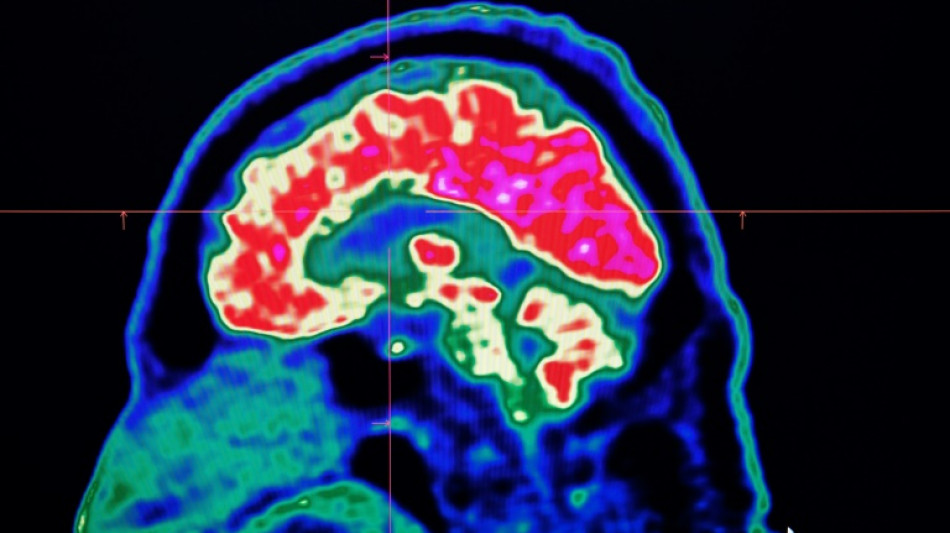

Surging nervous system disorders now top cause of illness: study

Conditions affecting the nervous system -- such as strokes, migraines and dementia -- have surged past heart disease to become the leading cause of ill health worldwide, a major new analysis said on Friday.

More than 3.4 billion people -- 43 percent of the global population -- experienced a neurological condition in 2021, far more than had previously been thought, the analysis found.

Lead study author Jaimie Steinmetz of the IHME said the results showed that nervous system conditions are now "the world's leading cause of overall disease burden".

The researchers looked at how 37 different neurological conditions affected ill health, disability and premature death across 204 countries and territories from 1990 to 2021.

More than 443 million years of healthy life were lost to nervous system disorders globally in 2021, an 18-percent increase from 1990, the study found.

Stroke, which was previously counted as a heart disease, was by far the worst neurological condition analysed, accounting for 160 million years of healthy life lost.

It was followed by a form of brain damage called neonatal encephalopathy, migraine, dementia including Alzheimer's disease, nerve damage from diabetes, meningitis and epilepsy.